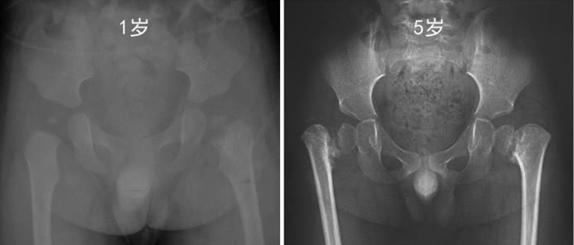

前几天,诊室里来了个5岁小男孩,父母介绍从孩子1岁开始就发现孩子走路摇摇晃晃的,带到当地医院去拍片,报告说没事,也就放心了,以为等孩子长大一些会好的,因为孩子没说疼痛不舒服,也就没在意。随着孩子越来越大,这种情况越来越明显,父母开始担心了,就带着孩子去医院再次就医,又给孩子做了骨盆正位X线片,这次报告提示孩子股骨颈干角小于正常范围,股骨颈干骺端与股骨头骺间明显增宽、碎裂的透亮带区域,股骨颈内下方还有不规则骨化,这个是儿童髋内翻的症状!!经验不足的话,容易误诊为股骨颈骨折不愈合或慢性股骨头骺滑脱。

髋内翻是由于孩子原发性软骨缺陷的发育性疾病。通过拍X片,我们可以看到我们的骨颈干角降低、股骨颈短缩、大转子相对的过度生长及患侧肢体短缩。这种表现在孩子出生时,表现并不明显,在孩子学会站立行走后,才逐渐表现出来。